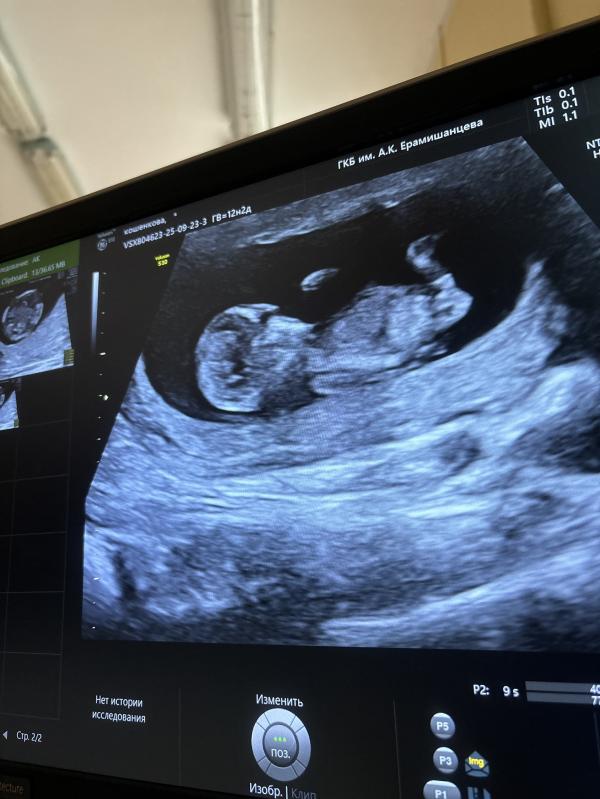

Мальчик или девочка )? Как думаете на снимке узи мальчик или девочка ? То что торчит это пуповина или половой бугорок 🙈? Погадаем ) 😅срок 12.1

Хотелось бы вам пожелать девочку, но кажется мальчик.. Ждите 20 неделю или анализ крови на y хромосому